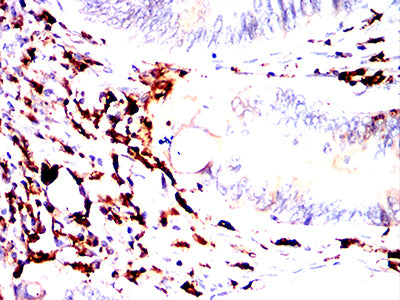

| IHC | 1/50-1/100 | Human,Mouse,Rat |

The MonoMethyl-p53 (Lys370) antibody is widely employed in cancer research to study p53 regulation in tumorigenesis, particularly in cancers with wild-type p53. It enables detection of this modification via techniques like Western blotting, immunohistochemistry, and immunoprecipitation, aiding investigations into p53's functional dynamics in cell lines, tissues, or patient samples. Studies using this antibody have provided insights into how Lys370 methylation affects p53-mediated tumor suppression, its crosstalk with other modifications (e.g., phosphorylation, acetylation), and its potential as a biomarker or therapeutic target. Researchers frequently apply it in models of colorectal, breast, and lung cancers to explore context-specific regulatory mechanisms. Proper validation with methylation-deficient mutants or enzymatic treatments is essential to ensure specificity in experimental settings.